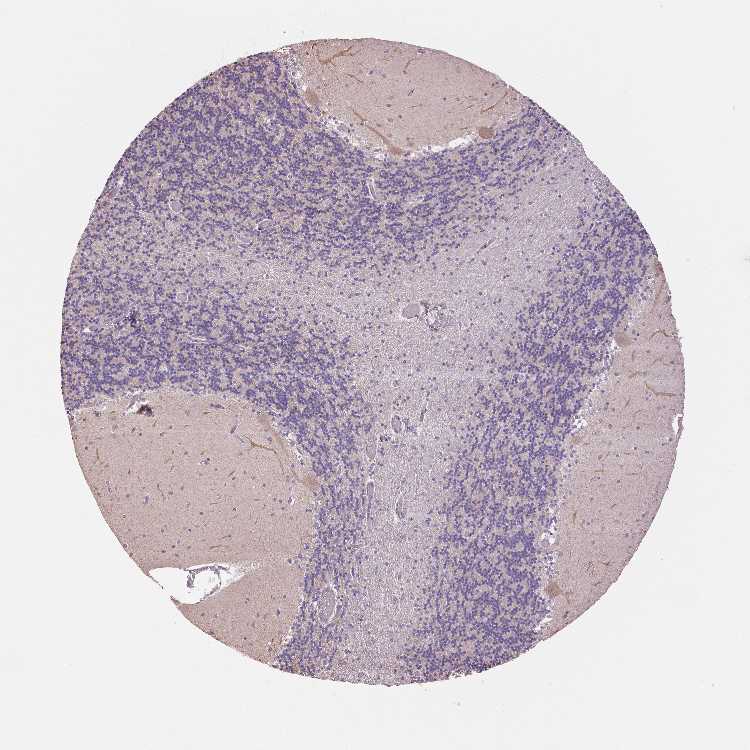

CEREBELLUM - Antibody stainingi

Antibody staining in the annotated cell types in the current human tissue is reported as not detected, low, medium, or high, based on conventional immunohistochemistry profiling in selected tissues. This score is based on the combination of the staining intensity and fraction of stained cells.

Each image is clickable and will lead to virtual microscopy that enables deeper exploration of all samples and also displays staining intensity scores, fraction scores and subcellular localization as well as patient and tissue information for each sample.

Antibody HPA036700

Purkinje cells Medium

Cells in granular layer Low

Cells in molecular layer Not detected